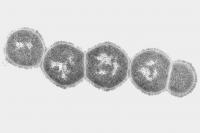

Recurrent Group A streptococcus (S. pyogenes) infections, which cause “strep throat,” have been linked to autoimmune neuropsychiatric disorders, notably Pediatric Autoimmune Neuropsychiatric Disorders associated with Streptococcal infections, or PANDAS. Children with PANDAS exhibit Tourette’s syndrome–like motor and vocal tics or obsessive-compulsive behaviors that appear to happen “out of the blue.”

The Strep A bacterial cell wall contains molecules similar to those found in human heart, kidney, or brain tissue, according to a co-leader of the study, Dritan Agalliu, PhD, assistant professor of pathology and cell biology (in neurology and pharmacology) at Columbia University Medical Center. These “mimetic” molecules are recognized by the immune system, which responds by producing protective antibodies. But because of this molecular mimicry, the antibodies react not only to the bacteria but also to the host tissues, producing autoantibodies that attack the body’s own tissues. Previously, scientists did not understand how these autoantibodies would gain access to the brain, because brain vessels form an extremely tight blood-brain barrier that prevents free movement of molecules, antibodies and immune cells from the blood into the brain.

A few years ago, researchers discovered that recurrent Strep A infections trigger the production of immune cells known as Th17 cells, a type of helper T cell, in the nasal cavity. But it was unclear how these Th17 cells lead to brain inflammation and symptoms such as those seen in children with PANDAS.